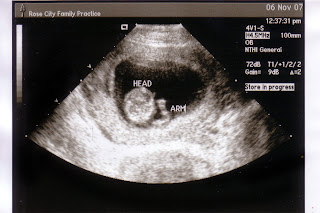

And: pregnant with Porter at 17 Weeks:

Ryan met me at my mom's work today so he could finally get to see his newest little boy. I had wanted to take my point and shoot camera to record and post a little video on here, but of course I forgot. (Our ultrasound in January we can take in a DVD to record it) He was measuring around 17w5days, so almost a week ahead of what he had measured before, and I believe that is almost 2 weeks ahead of what the doctors have me at. (Their due date is June 1, but the ultrasound keeps saying May 23). I guess when I go in in January they can decide what they want to do. I guess it really doesn't matter because the baby will come whenever he is ready, right?

Anyhow, we got a buttload of pictures. Baby Boy was all snuggled in cozy looking. We got to see a lot of his face, eyes, hands and cute little feet. He was moving his arms all around, stretching them over his head and playing with his face. I can't wait to meet him!

I'm also getting so excited to see this little guy. I'm thrilled that, so far, he looks healthy and happy and as cute as a little 2D baby on an ultrasound can look. I keep wondering if he'll look like Porter, or if he'll have Ryan's dark eyes rather than my and Porter's hazel eyes. Will he have dark dark hair like Ryan, or medium brown like Porter and I? Will he have my nose or Ryan's? Will he be a good baby, as Porter was, or will he be my hellion child? Will he be a talker like Porter or quiet and reserved? All those things just have me so excited to see him in May!